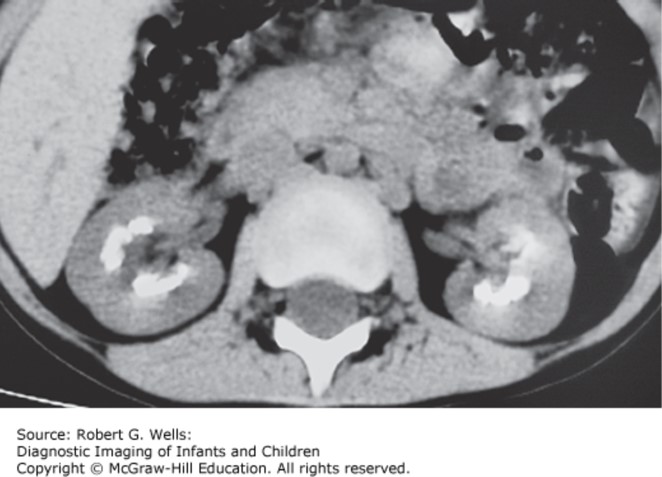

Photo: Wells RG. Diagnostic Imaging of Infants and Children; 2015.